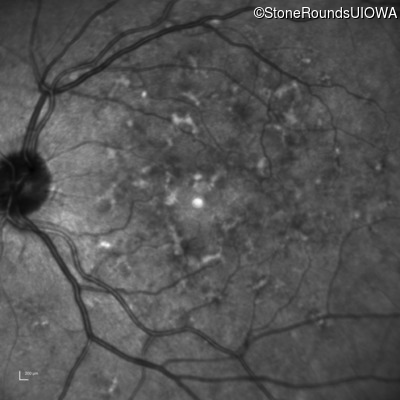

Infrared Fundus Photograph - Left - 20/20 -2

Exemplar